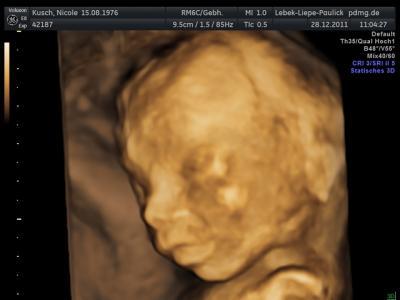

hab am 24 meinen kids gesagt das ich schwanger bin. ich hab einfach ein geschenk eingepackt mit einen body drin auf´m geschenk stand an ??? das kam voll lustig an und heute war outing große untersuchung und es wird

und nach dem ich es den Kids gesagt hatte hab ich jetzt auch einen richtigen bauch und er ist ganz schön aktiv wollte sich nicht zeigen, aber sein pullermann hat er ganz deutlich gezeigt.

Das Bild ist auch voll niedlich. Hoffe, dass ich bei der FD am 5.1.auch ein schönes Bild bekomme.

Herzlichen Glückwunsch zum Jungen und ein süsses Bildchen

Glückwunsch zum Prinzen!!!